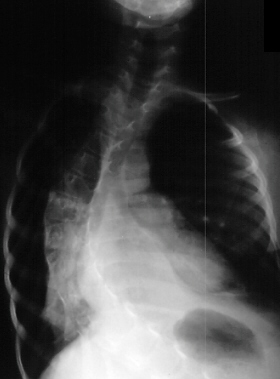

Age 6 scoliosis progressed to 78 degrees

and PSF with the unit rod

was performed.

- Spinal Deformity

- 100% of type II, and most of Type III develop scoliosis with resulting

decrease in pulmonary function

- Typically begins in the first decade of life, is progressive and resistant

to bracing